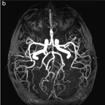

Angiografía

Cerebral Diagnóstica

Los motivos para realizar una angiografía cerebral diagnóstica son múltiples. Usualmente la realizamos a través de la arteria femoral, localizada en la ingle, utilizando pequeños tubos muy delgados y largos (catéteres) hasta las arterias del cuello, guiándonos por imágenes por rayos X. Desde las arterias del cuello se realizan proyecciones craneales observando de forma nítida las estructuras vasculares cerebrales, así como la información detallada del flujo sanguíneo cerebral. En la mayoría de los casos este procedimiento se realiza solo con anestesia local en el sitio de la punción en la ingle.